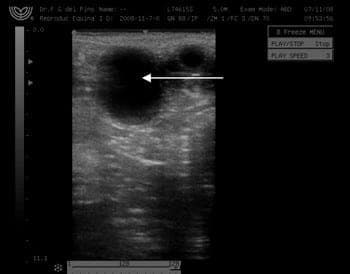

Primera Transferencia Embrionaria doble en una yegua de raza Peruana de Paso laureada - Image 2

Ecografía del ovario izquierdo de la yegua donante donde también se observa otro folículo en desarrollo próximo a ovular.